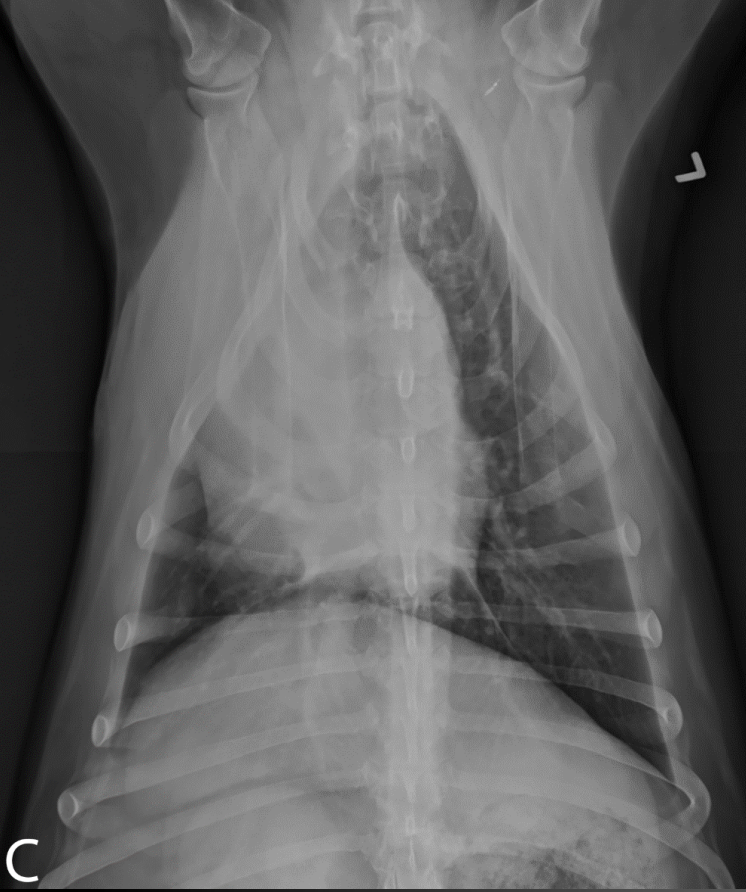

What is shown in these images?

A

generalized lymphadenopathy:

-widening of mediastinum

-deviation of mainstem bronchi